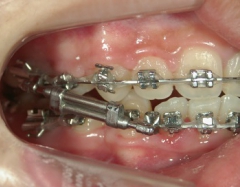

矯正歯科 治療途中 下顎の後退を改善する為、ツインフォースで下顎を前に出す

no.18_2196_治療中_右.jpgno.18_2196_治療中_正面.jpgno.18_2196_治療中_左.jpg